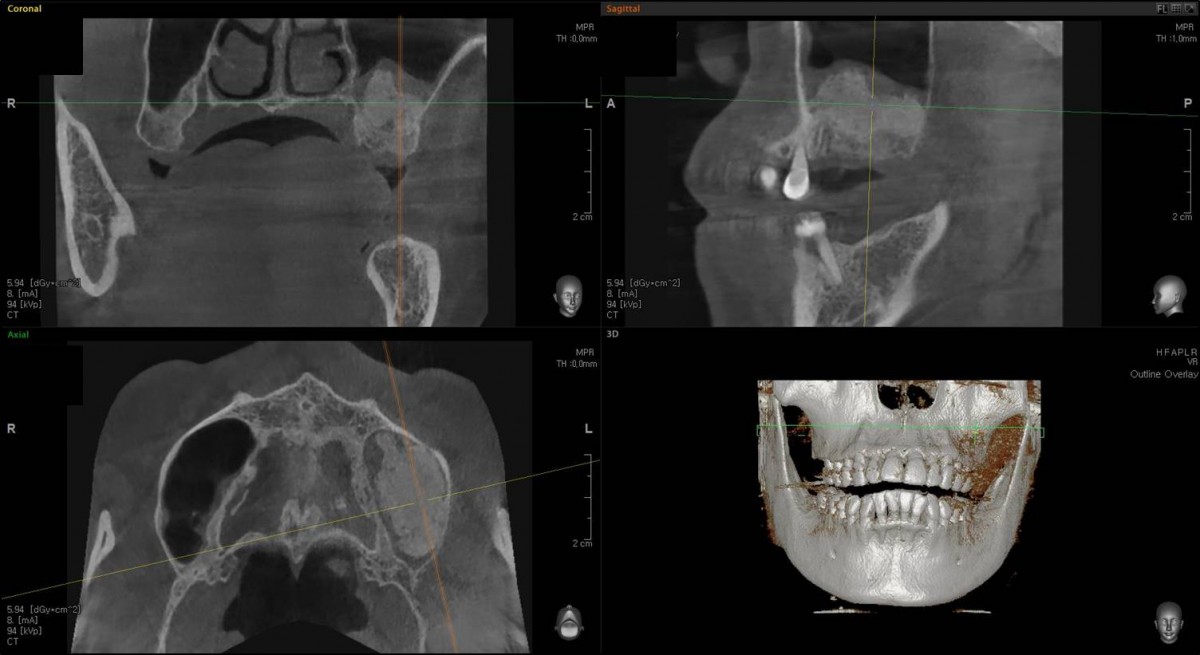

Implant in the molar zone of both jaws

A 55-year-old female patient had

bilateral problems in both jaws.

It was decided to proceed with implant-supported restoration in the left molar part first.

She had been taking hypertension medication for a long time.

▲Panoramic radiograph before the implant surgery in the lower left area.